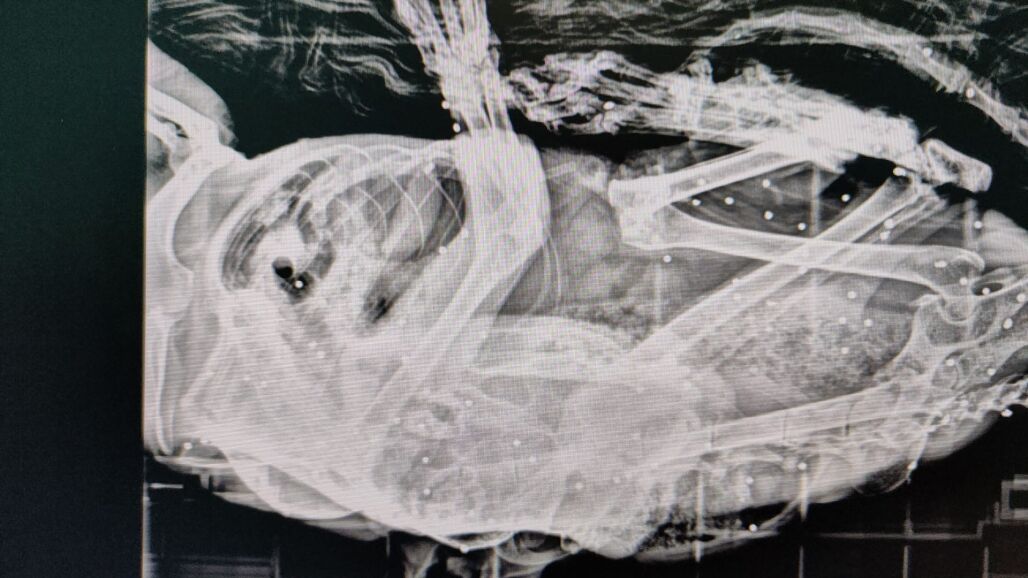

Ante la mala evolución del animal, llamado Van Gogh, fue trasladado al veterinario, donde las radiografías que le hicieron revelaron la presencia de decenas de impactos de perdigón en su interior. La Federación DEAN (Defensa Animal Cantabria), en la que se integra Gatucos Torrelavega, ha sido quien ha dado a conocer estos hechos.

Según la entidad, la elevada cantidad de perdigones descarta por completo la posibilidad de un disparo accidental. "Todo apunta a un acto deliberado, prolongado y con ensañamiento", señalan, ya que un único disparo habría provocado la huida instintiva del animal. La acumulación de impactos solo puede explicarse, a su juicio, por una acción consciente y reiterada.